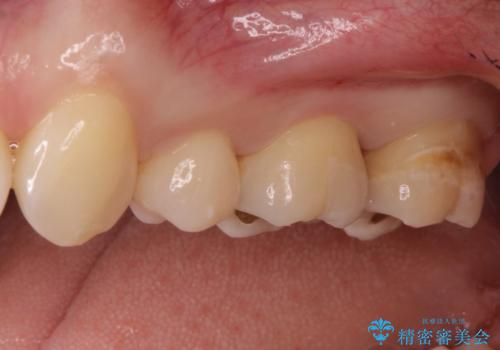

- 他院で虫歯になっていると指摘され来院されました。適合の良いゴールドインレーによる治療がされていましたが、違う部分が虫歯になってしまっていました。審美性の良いセラミックインレーを希望されました。

ゴールドインレーを除去し、その下で広がっていた虫歯をきれいに取り除きました。